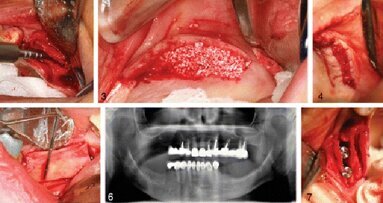

Денталните техники, модифициращи алвеоларния гребен, се използват от много години, ...